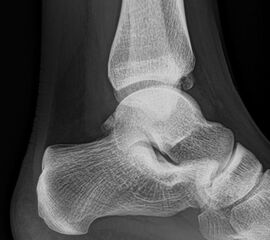

Sprunggelenk lateral ohne Belastung

Positionierung:

• Patient liegt auf dem Rücken und dreht den Fuß des aufzunehmenden Beins so nach innen, dass beide Malleolen genau übereinanderstehen.

• Die laterale Fuss-Seite liegt auf der Kassette, das Sprunggelenk ist 90° angewinkelt.

• Der Zentralstrahl wird zentral auf das Sprunggelenk gerichtet.

Kennzeichen des Röntgenbildes:

• Oberes und unteres Sprunggelenk sind rein seitlich abgebildet, inklusive Kalkaneus.

• Die Malleolen kommen übereinander zu liegen.

• Tibiagelenkfläche und Talusrolle werden exakt seitlich dargestellt, es kommt zu keinen Doppelkonturen.

• Die Fibula projiziert sich ins mittlere bis hintere Drittel der Tibiagelenkfläche.

• Die vordere und hintere Tibiakante, das Chopart-Gelenk und das Subtalargelenk kommen zur Darstellung.

• Das proximale Ende des Os metatarsale V ist mit abgebildet.

• Der Weichteilmantel (Achillessehne) ist erkennbar.

Besondere Bemerkungen zum Beispielbild:

• Patient mit anamnestisch chronischer OSG Instabilität.

• Ventral der Tibia findet sich ein abgebrochener Osteophyt.

Zur Vollansicht und zum Lesen der Bildbeschreibung bitte die Bilder anklicken.